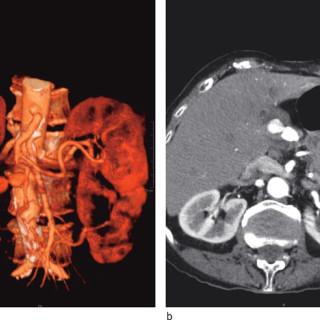

Sentrale venekatetre brukes rutinemessig i pasientbehandlingen ved norske sykehus. Den sentralvenøse tilgangen oppnås gjennom punksjon av v. jugularis interna, v. subclavia eller v. femoralis. Komplikasjoner knyttet til bruken ses både i forbindelse med selve innleggingen av kateteret, når kateteret er på plass og i bruk og når det skal fjernes. Komplikasjoner knyttet til innlegging av et sentralvenøst kateter er punksjon av nærliggende arterie, pneumothorax, arytmier, skade av plexus brachialis, skade på ductus thoracicus, luftembolisering og feilposisjonering av kateteret (1, 2)...